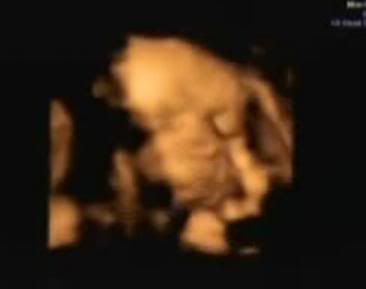

you got the 3D scan!

It's creepy, yet amazing, innit?